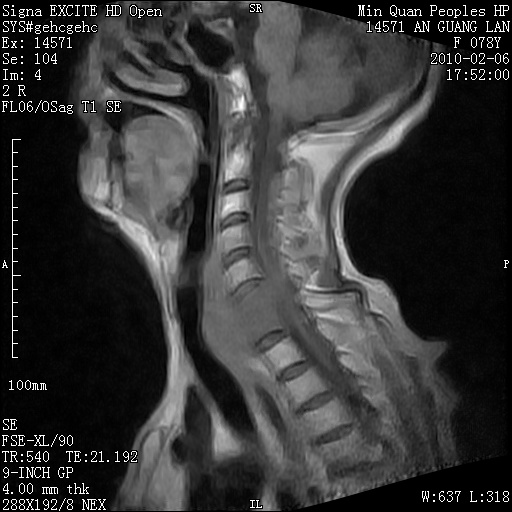

标题: MRI2763:C6、C7椎体病变性质?

f,78y,颈部与双上肢阵发性剧痛40余天。ct可见c6、c7椎体虫蚀样破坏,其间椎间隙变窄(没有图片资料可供上传)。

考虑椎体结核并椎旁脓肿。